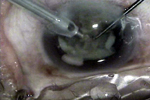

过熟期过熟期硬核白内障软壳技术

手术者-温州医学院眼视光医院 赵云娥主任

部分视频画面